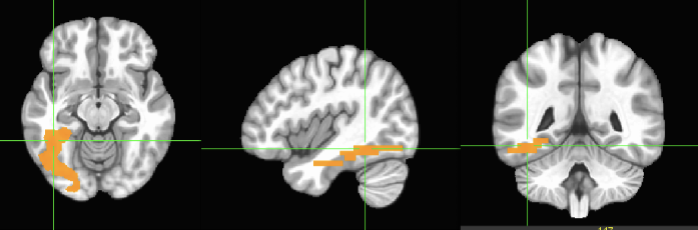

SUBSTANTIA NIGRA– This is the left hemisphere, we have a

right SN as well. Both, left and right, are important

synthesizers of Dopamine. The other important synthesizer of

DA in the brain is the VTA, which is next to the SN.